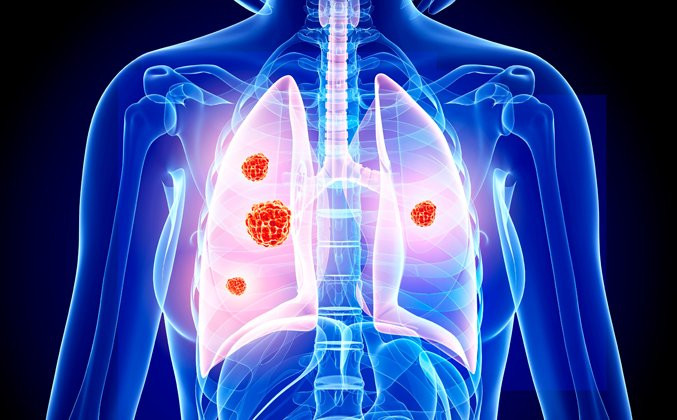

TAG: kanker paru

kanker paru

"Kanker Paru"